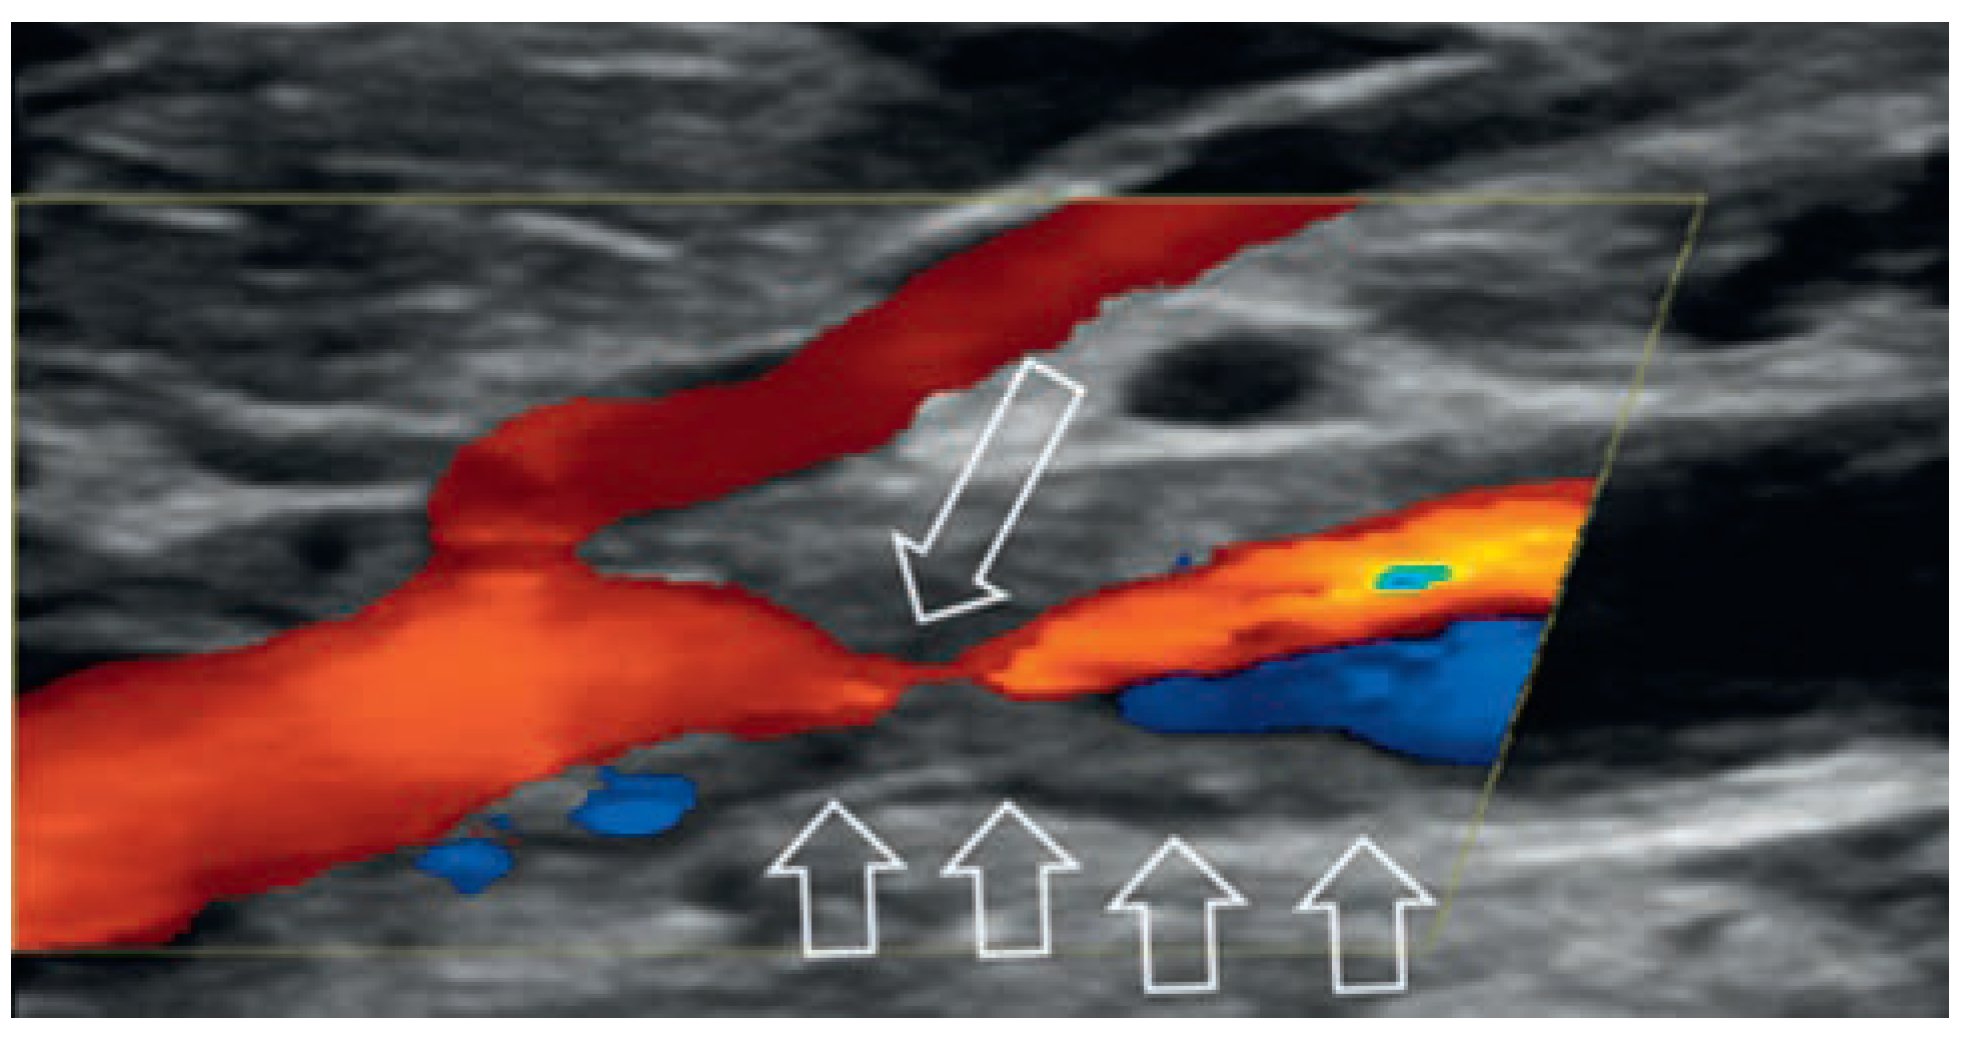

Venöse Malformationen

Kapillär-lymphatisch-venöse Malformation mit Überwuchs (Klippel-Trénaunay-Syndrom)

Arterielle Malformation und arteriovenöse Fistel